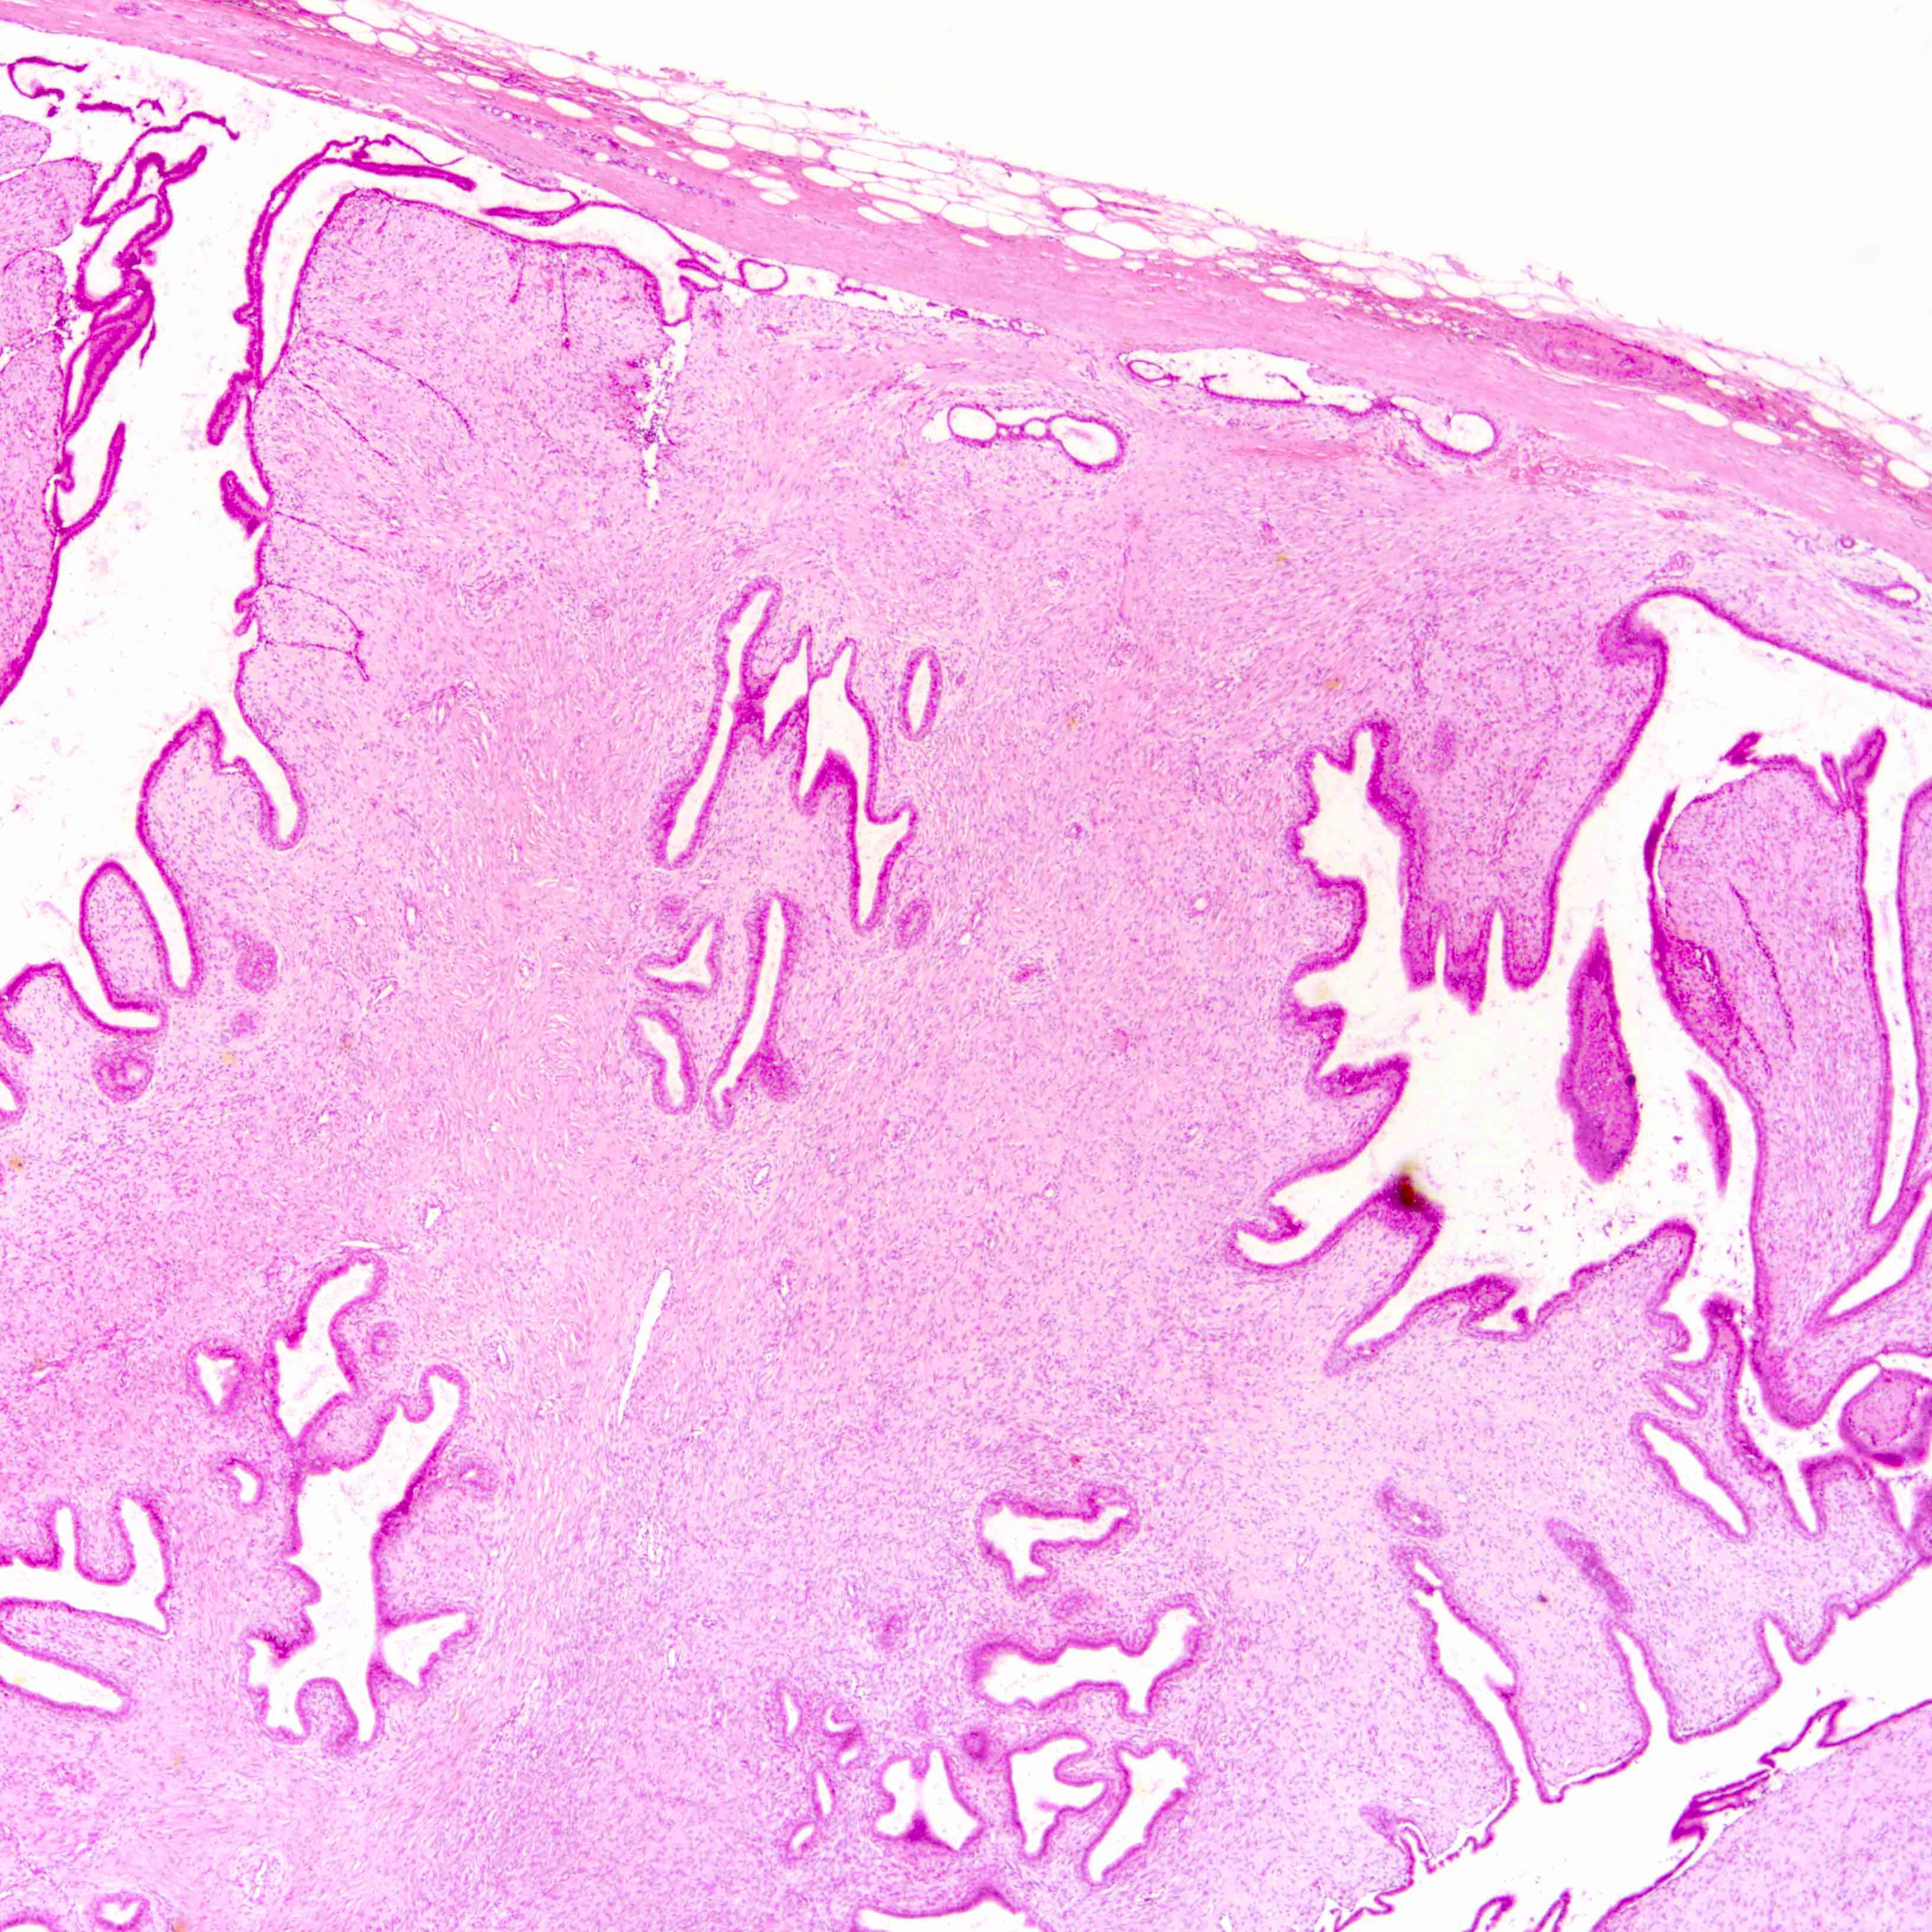

Microscopic (histologic) images

Contributed by Joshua J.X. Li, M.B.Ch.B. and Gary M. Tse, M.B.B.S.

Benign phyllodes tumor

Malignant phyllodes tumor